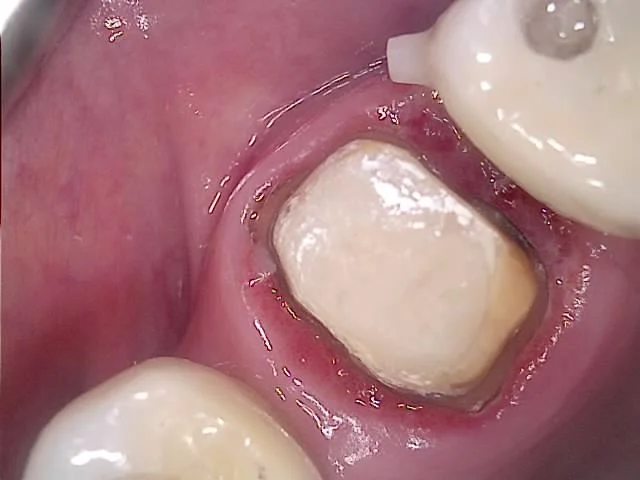

임플란트 기둥 크라운 재제작 과정

임플란트 뿌리는 그대로, 기둥과 크라운만 재제작

임플란트 뿌리는 그대로 둔 채 기둥과 머리만 새로 제작합니다^^

재제작 크라운 적합 확인 사진

새 크라운 적합 확인 — 틈새 사라진 모습

긴밀한 사이 틈 복원 완료 사진

긴밀해진 사이 틈 — X-ray로 확인

치료 후 잇몸 회복 결과 사진

치료 후 — 잇몸이 예쁘게 아문 모습

긴밀해진 사이 틈을 육안으로도 X-ray로도 확인할 수 있고, 주변 잇몸도 예쁘게 아문 것을 확인할 수 있습니다^^